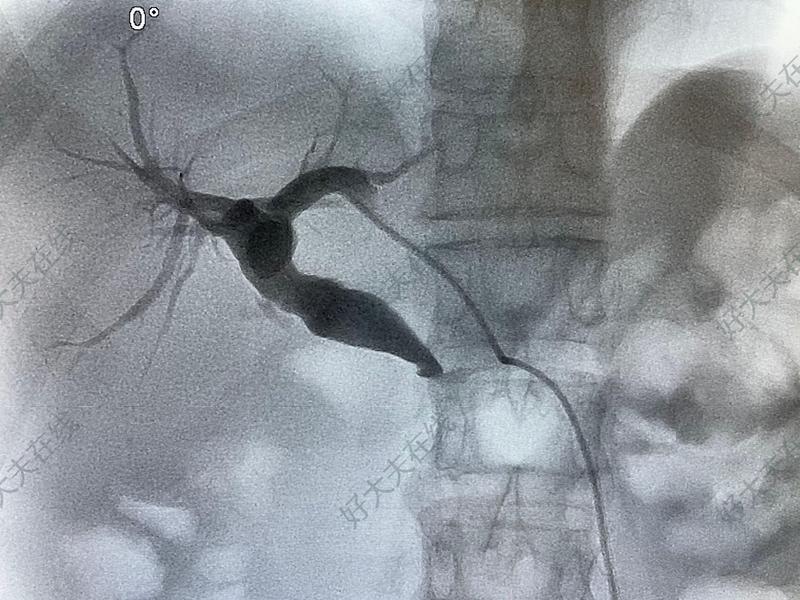

治疗前 老年患者,因皮肤黏膜发黄、巩膜黄染,上腹痛,消瘦,就诊我院,CT发现胰腺肿物、胆管扩张,考虑胰腺癌合并梗阻性黄疸。 治疗中 遂行经皮肝穿胆道引流,排出胆汁后,4~5天,症状缓解。再行胆道球囊扩张、胆道支架植入。 治疗后 治疗后7天 恢复正常进食,体力情况改善。